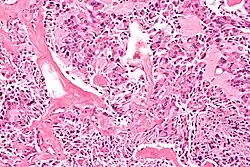

Multiple endocrine neoplasia (abbreviated MEN) is a condition which encompasses several distinct syndromes featuring tumors of endocrine glands, each with its own characteristic pattern. In some cases, the tumors are malignant, in others, benign. Benign or malignant tumors of nonendocrine tissues occur as components of some of these tumor syndromes.